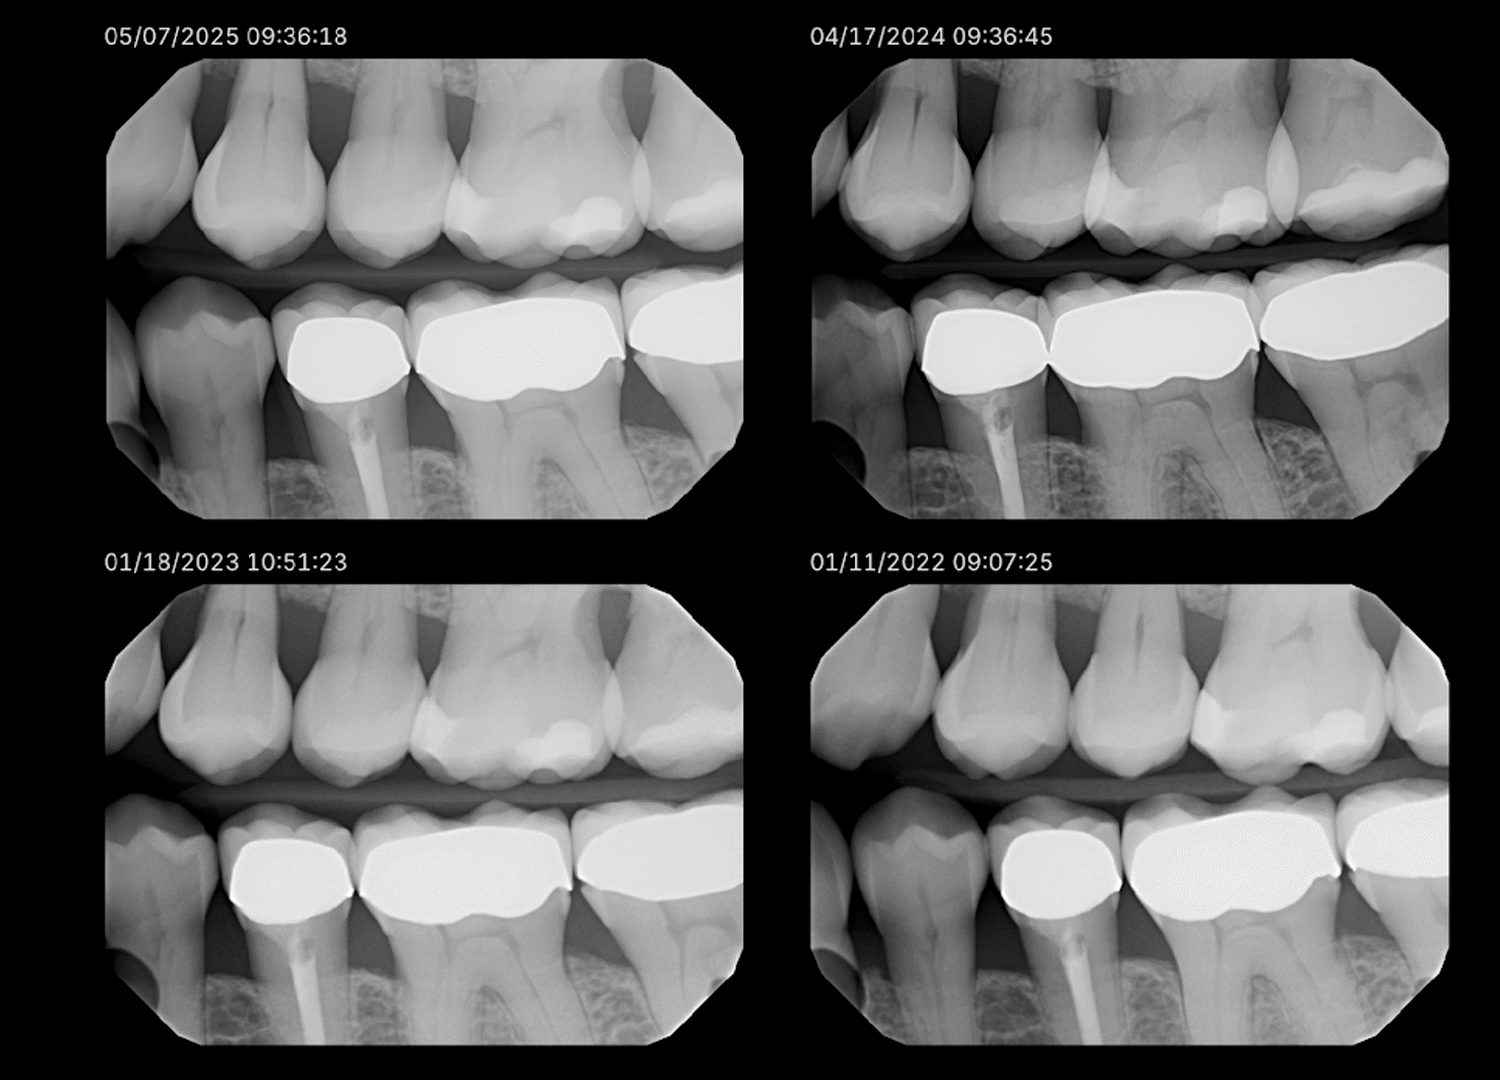

One of my longtime patients has had routine bitewing radiographs taken nearly every year. The last four years of these radiographs were analyzed through Overjet’s AI platform. When I compared one year to the next, everything appeared stable. But when I compared the first and fourth year side by side, a new story emerged. With the help of AI, I discovered she had lost about 0.5 to 0.8 millimeters of bone height. That may sound minimal, but in the world of periodontics, it signals an active process that warrants attention.

Modern AI visualization tools such as LENS allow radiographs from different years to be viewed side by side, each displaying its respective bone measurements. This view gives clinicians and patients a clear perspective on how small, nearly invisible changes accumulate over time.